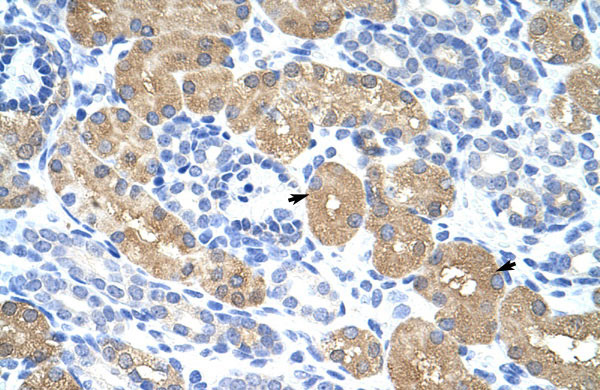

Rabbit Anti-RAE1 Antibody Paraffin Embedded Tissue: Human Kidney Cellular Data: Epithelial cells of renal tubule Antibody Concentration: 4.0-8.0 μg/ml Magnification: 400X